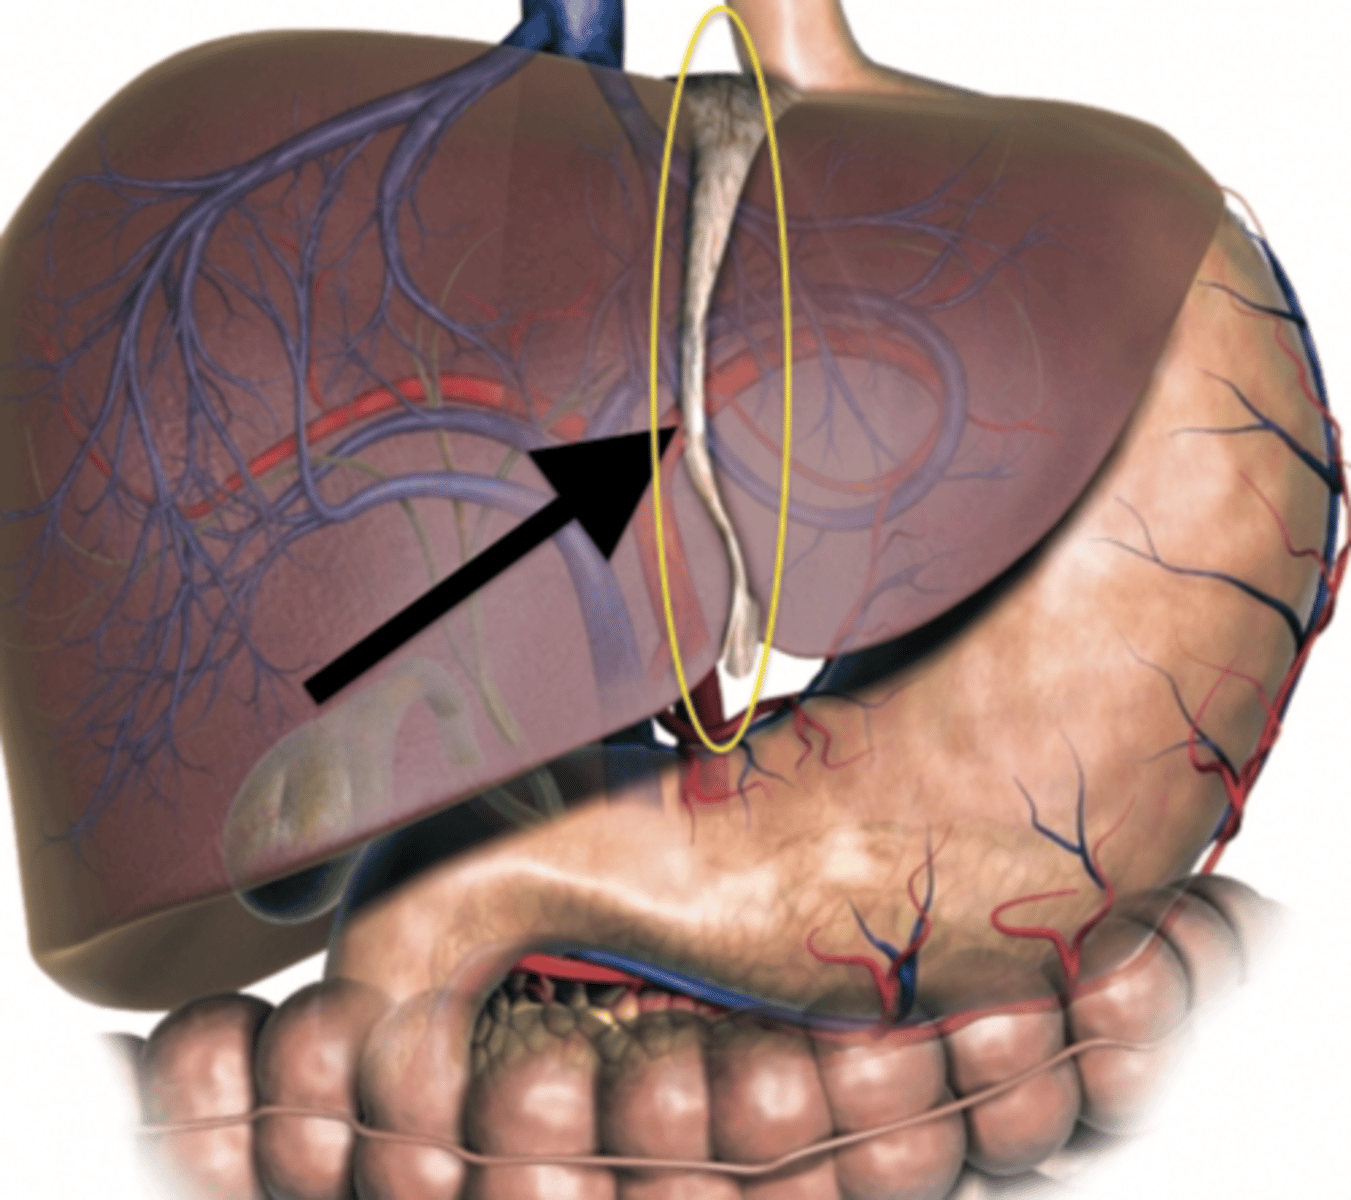

Right Lobe of Liver

Left Lobe of Liver

Caudate Lobe of Liver

Quadrate Lobe of Liver

Falciform Ligament

Ligamentum Teres